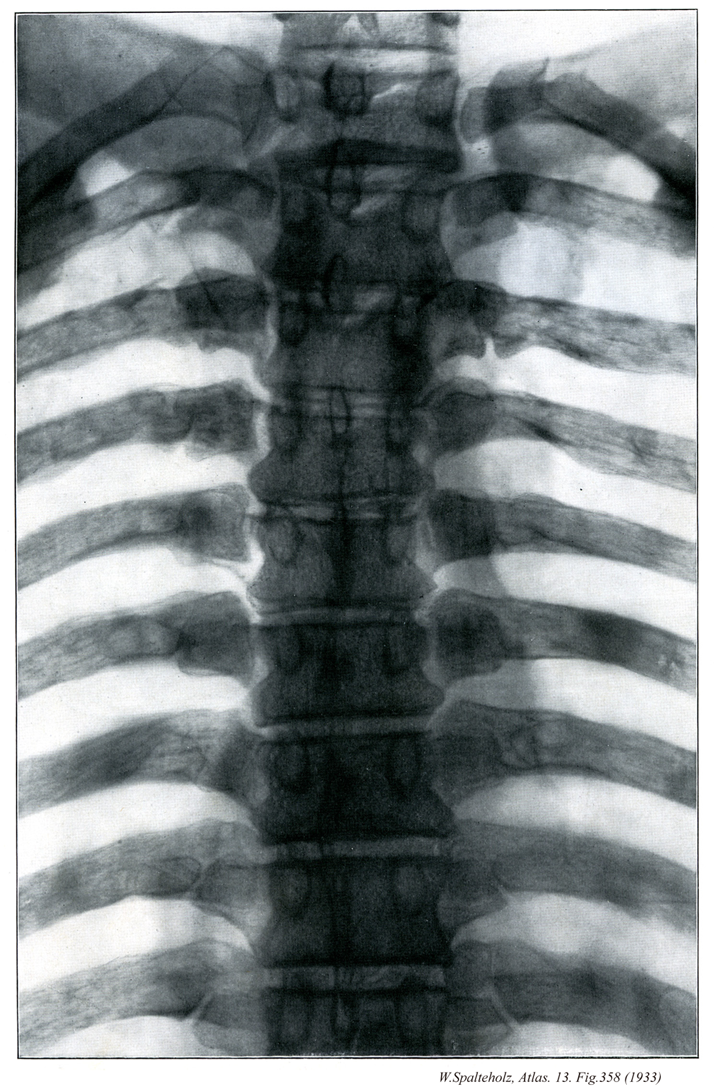

358

- 358_00【Thoracic vertebrae [TI-TXII]胸椎[T1-T12] Vertebrae thoracicae [T I-T XII]】 The twelve thoracic vertebrae.

→(胸椎は頚椎につづく12個の椎骨で、肋骨と結合して胸郭を形成する。椎体は下位のほど大きい。また、椎体の高さは頚椎より高く、腰椎より低い。椎体の外側面後部には肋骨頭に対する関節窩、すなわち、肋骨窩があり、第二~第九胸椎では椎体の上縁と下縁にそれぞれ半円形の上肋骨窩、下肋骨窩がある。第一~第九胸椎では互いに隣り合う胸椎の下および上肋骨窩が1個の関節窩を作り、一個の肋骨頭と関節する。第一胸椎には半円形の下肋骨窩があり、第十胸椎では上関節窩だけが存在する。また、第十一境地では椎体の上縁に、第十二胸椎では椎体のほぼ中央に1個の円形の肋骨窩がある。胸椎の椎孔はほぼ円形をしており、頚椎の椎孔に比してかなり小さい。横突起は第八胸椎でもっとも大きく、これより上位または下位の胸椎では、第八肋骨から遠ざかるほど小さくなる。第一~第十胸椎では横突起の尖端の前面に円形の関節面があり、横突肋骨窩という。第十一および第十二胸椎の横突起には横突肋骨窩はみられない。境地の棘突起は三角柱のような形をしていて、第1胸椎から第八胸椎までは下位になるほど傾斜が強くなる。しかし、その後は次第に傾斜が弱まり、第十二胸椎ではほとんど水平である。)

- 358_00a【Ribs [I-XII]肋骨[1-12] Costae [I-XII]】

→(肋骨という名前は、骨質からなる肋硬骨と軟骨質からなる肋軟骨の総称である。肋骨は扁平長骨で、12対あり、後方で胸椎と連結して胸郭を構成する。軟骨性骨として発生するが、前方の小部分が肋軟骨として軟骨のまま残る。第一~七肋骨は前端が胸骨外側縁と連結しているが、第八から十二肋骨は胸骨に達していない。前者が真肋、後者が仮肋である。仮肋のうち第八~第十肋骨では、肋軟骨が上位の肋軟骨と結合して肋骨弓を形成する。第十一・第十二肋骨は自由端で終わる(浮遊肋骨)。肋骨は後上方から前下方へ向かい、胸骨近くで角をなし、上方へ向かう。第一・第二肋骨では肋軟骨との境界部で、他の肋骨では肋軟骨部で曲がっている。長さは第一肋骨~第七肋骨まで増加し、第八肋骨以下では減少する。胸椎体と連結する膨大した部分が肋骨頭で、肋骨頭関節面がある。第二~第十肋骨では水平に走る肋骨頭稜によって、上位胸椎体の下肋骨窩に対する上方の小さな関節面と、各肋骨と同順位の胸椎体の上肋骨窩に対する下方の大きな関節面とが区別される。第一・第十一・第十二肋骨では、肋骨と同順位の胸椎体とのみ連結するので、肋骨頭関節面は単一な平面である。肋骨体に続く前後にやや扁平な部分がが肋骨頚で、各肋骨と同順位の胸椎横突起の前面に位置している。鋭い上縁が肋骨頚稜で、後面は粗面をなす。外側端後部外面の膨隆した部分が肋骨結節で肋骨体との境をなす。肋骨結節には、各肋骨と同順位の胸椎横突起に対する下内側部の肋骨結節関節面と、外側部の靱帯が付着する隆起とがある。肋骨結節に続く扁平な部分が肋骨体で、上縁は丸く下縁は鋭い。肋骨結節の外側で、前後にやや厚く後面が粗面をなし、肋骨がやや強く弯曲する部分が肋骨角である。第一肋骨の肋骨角は肋骨結節の所にあるが、第二肋骨以下下方の肋骨ほど、肋骨角は肋骨結節の外側方に位置するようになる。肋骨体内面下部で、肋骨頚から前方に走る溝が肋骨溝で、肋間神経・肋間動静脈が入る。溝は前端近くで不明瞭となる。肋骨体の前端は被厚し、断端は楕円形の凹面として終わる。肋骨は内側方へ屈曲するとともに、長軸のまわりで上縁が内側方向へねじれている。第三から第十肋骨は上述の一般的形態を示すが、第一・第二・第十一・第十二肋骨はやや変形を示す。第一肋骨は最も短く、上下に扁平なため幅が最も広い。肋骨角に相当する部分は肋骨結節に一致し、ここで弯曲が最も強い。上面の中央内縁に近い部分の小隆起が前斜角筋結節で、この前方にある浅い陥凹が鎖骨下静脈溝、後方の浅い陥凹が鎖骨下動脈溝である。第二肋骨の上面中央外側部の粗面が前鋸筋粗面である。)